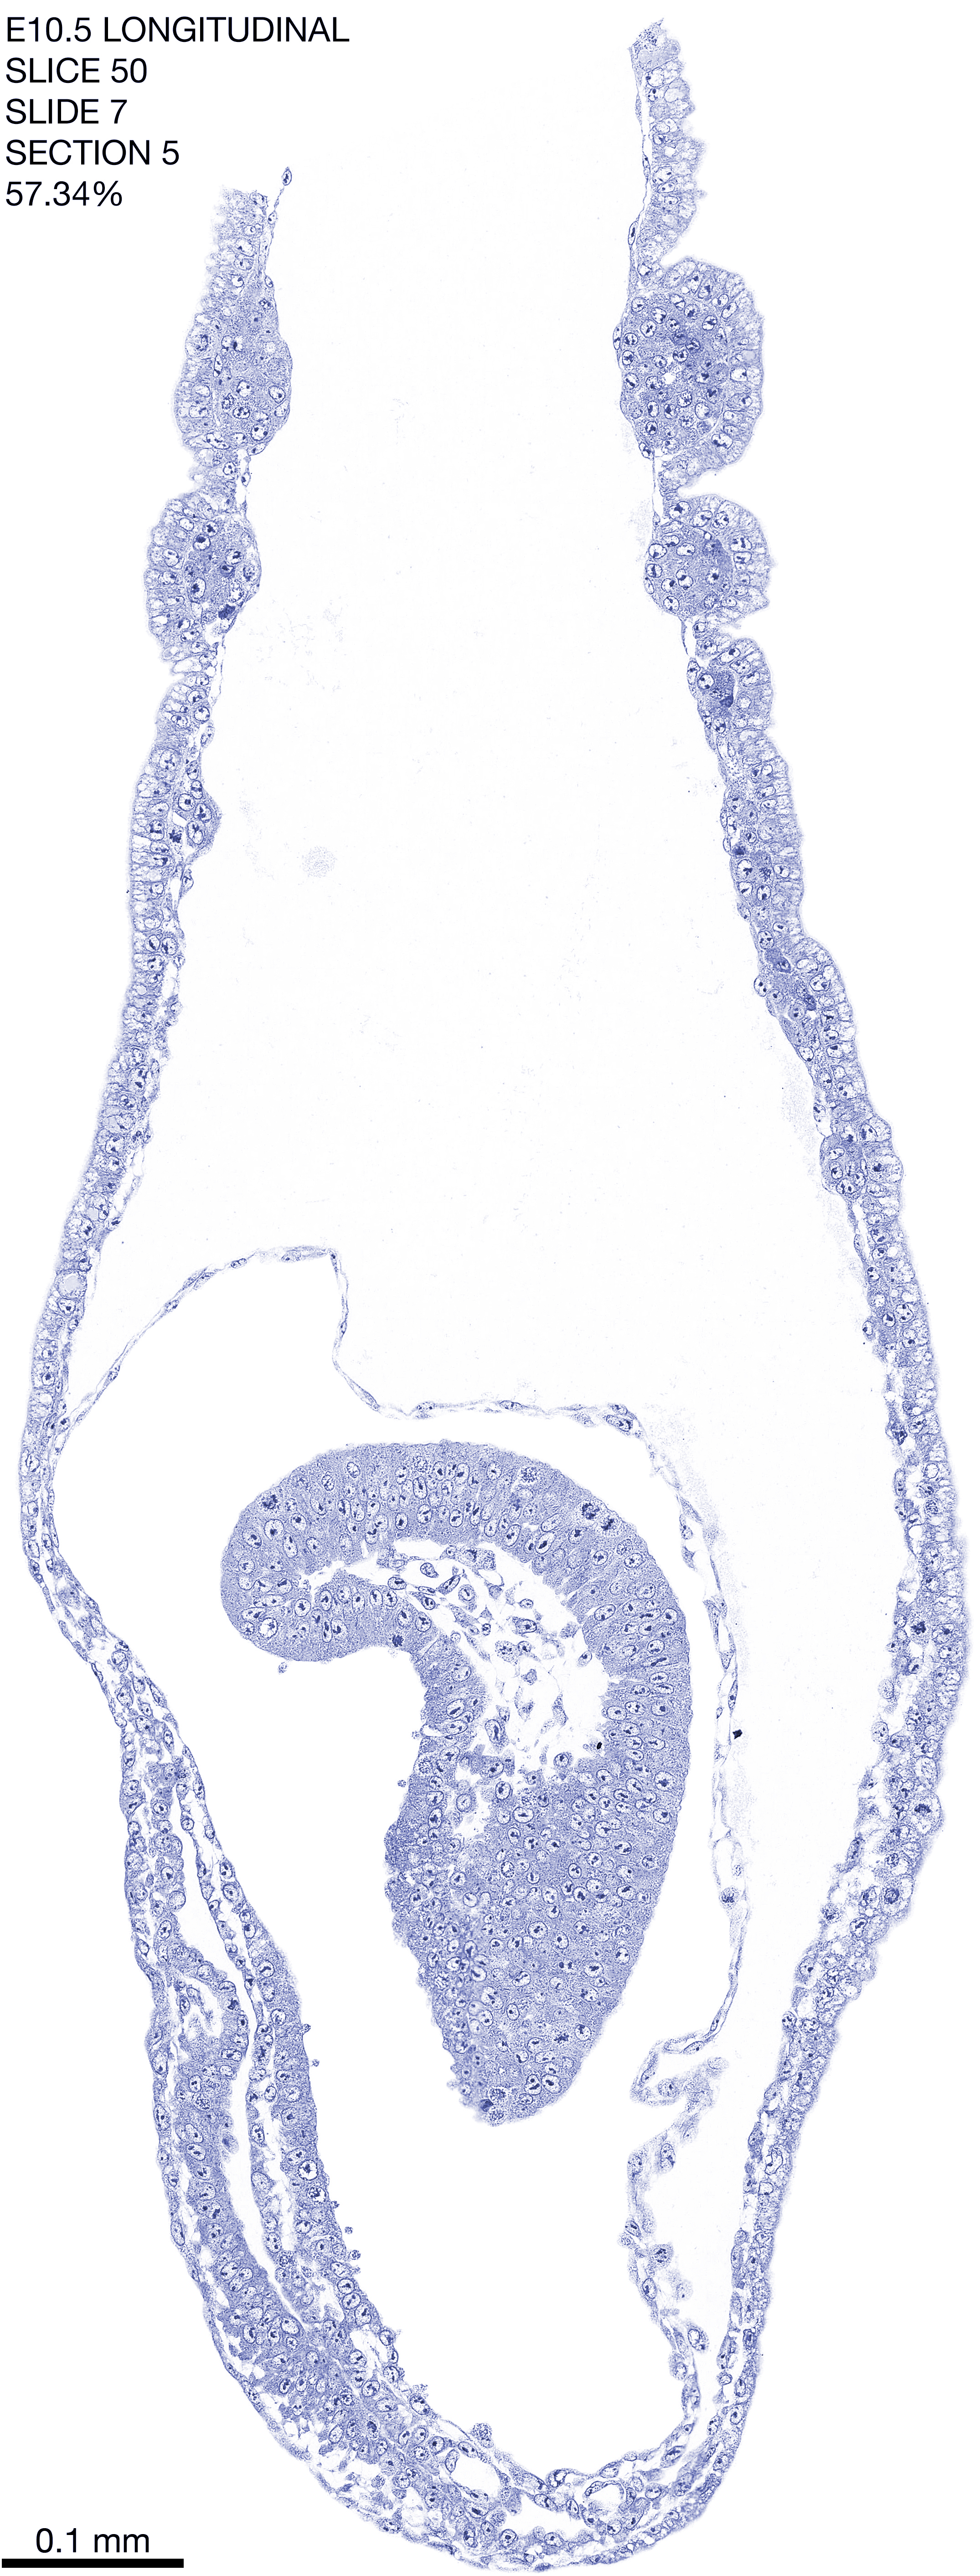

E10.5 Longitudianal Archive This page contains jpg files of ALL SLICES (each 3µm thick) that were scanned of the E10.5 longitudinally cut specimen. Download: Large | High Res Download: Large | High Res Download: Large | High Res Download: Large | High Res Download: Large | High Res Download: Large | High Res Download: Large | High Res Download: Large | High Res Download: Large | High Res Download: Large | High Res Download: Large | High Res Download: Large | High Res Download: Large | High Res Download: Large | High Res Download: Large | High Res Download: Large | High Res Download: Large | High Res Download: Large | High Res Download: Large | High Res Download: Large | High Res Download: Large | High Res Download: Large | High Res Download: Large | High Res Download: Large | High Res Download: Large | High Res Download: Large | High Res Download: Large | High Res Download: Large | High Res Download: Large | High Res Download: Large | High Res Download: Large | High Res Download: Large | High Res Download: Large | High Res Download: Large | High Res Download: Large | High Res Download: Large | High Res Download: Large | High Res Download: Large | High Res Download: Large | High Res Download: Large | High Res Download: Large | High Res Download: Large | High Res Download: Large | High Res Download: Large | High Res Download: Large | High Res Download: Large | High Res Download: Large | High Res Download: Large | High Res Download: Large | High Res Download: Large | High Res Download: Large | High Res Download: Large | High Res Download: Large | High Res Download: Large | High Res Download: Large | High Res Download: Large | High Res Download: Large | High Res Download: Large | High Res